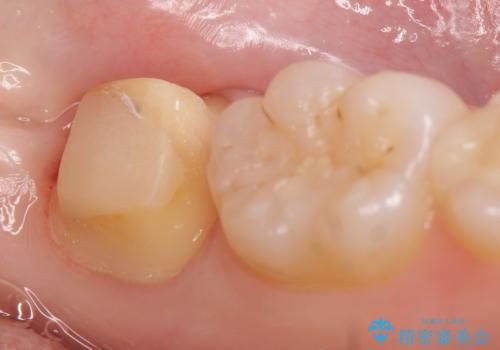

左下7遠心(下記のX線写真の左側)の歯質が歯肉縁下でかつポケットも深かったため、歯茎を下げる歯周外科を行いました。

その後歯茎の治りを待ちポケットが正常値であることを確認後、オールセラミッククラウンによる補綴を行いました。

今回用いたオールセラミッククラウンはジルコニアフレームという白い素材の上にセラミックを盛っているため、審美性が非常に高いのが特徴です。

また、ジルコニアは人工ダイヤモンドの材料にも使われているほど高い強度を持っており、そのためオールセラミッククラウンは審美性だけでなく、奥歯やブリッジの補綴も可能とするクラウンです。